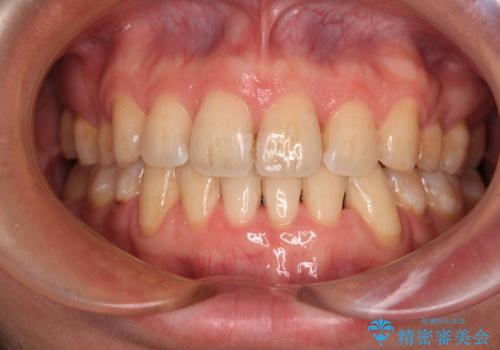

顎が左右にずれた咬み合わせ ハーフリンガルの抜歯矯正

- 口元の突出感を気にして来院された患者様です。

目立たない装置を希望され、上顎が裏側装置で下顎が表側装置のハーフリンガルを希望されました。

上下の顎骨が左右に大きくずれており、奥歯が交叉咬合となっていたため、ハーフリンガルよりも表側装置をおすすめしましたが、目立たない装置を強く希望されたため、治療期間が長期化することを前提に、ハーフリンガルにて抜歯矯正を行うこととしました。

裏側装置での交叉咬合改善は非常に困難なもので、頻繁に装置の脱落がありました。

それでも想定以上に治療期間は長期化せず、咬み合わせも口元も満足のいく仕上がりとなりました。